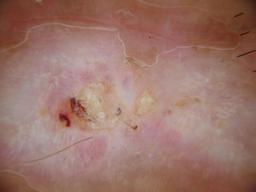

{

"age_approx": 85,

"anatom_site_general": "lower extremity",

"concomitant_biopsy": true,

"dermoscopic_type": "contact non-polarized",

"diagnosis_1": "Malignant",

"diagnosis_2": "Malignant epidermal proliferations",

"diagnosis_3": "Squamous cell carcinoma, Invasive",

"diagnosis_4": "Squamous cell carcinoma, Invasive, Keratoacanthoma-type",

"diagnosis_confirm_type": "histopathology",

"image_type": "dermoscopic",

"melanocytic": false,

"patient_id": "IP_0740576",

"personal_hx_mm": false,

"sex": "male"

}